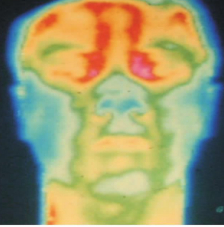

△通过红外热成像判断,为正常头面部

△右侧周围型面瘫,瘫痪侧略偏高温